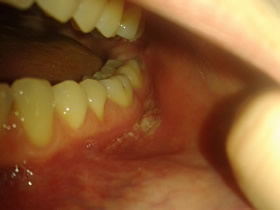

Despite these Prednisolone Blues, it’s still a better quality of life than living without them. Stupidly, earlier this year I decided to take a break from them and within a week my entire mouth and throat started to flare. I was in so much pain and discomfort that it hurt to talk, drinking water felt like I had a mouth full of glass shards. I struggled on for two weeks, the agony increasing as the days went on. I lost 8lb’s in a very short space of time, dropping back to 6st 12lb. I became extremely weak and dehydrated through lack of intake and so was admitted back to hospital on Easter Monday. A week of strong IV steroids and antibiotics, things rapidly improved and I was dischaged and have continued on oral prednisolone ever since. These photographs were taken earlier this year; you can clearly see the agonising, itchy inflammation on my face. The oral side of things don’t appear to be particularly problematic, but you can only really see the tip of the iceberg, so-to-speak, as the problem is deeper set in to the gums.